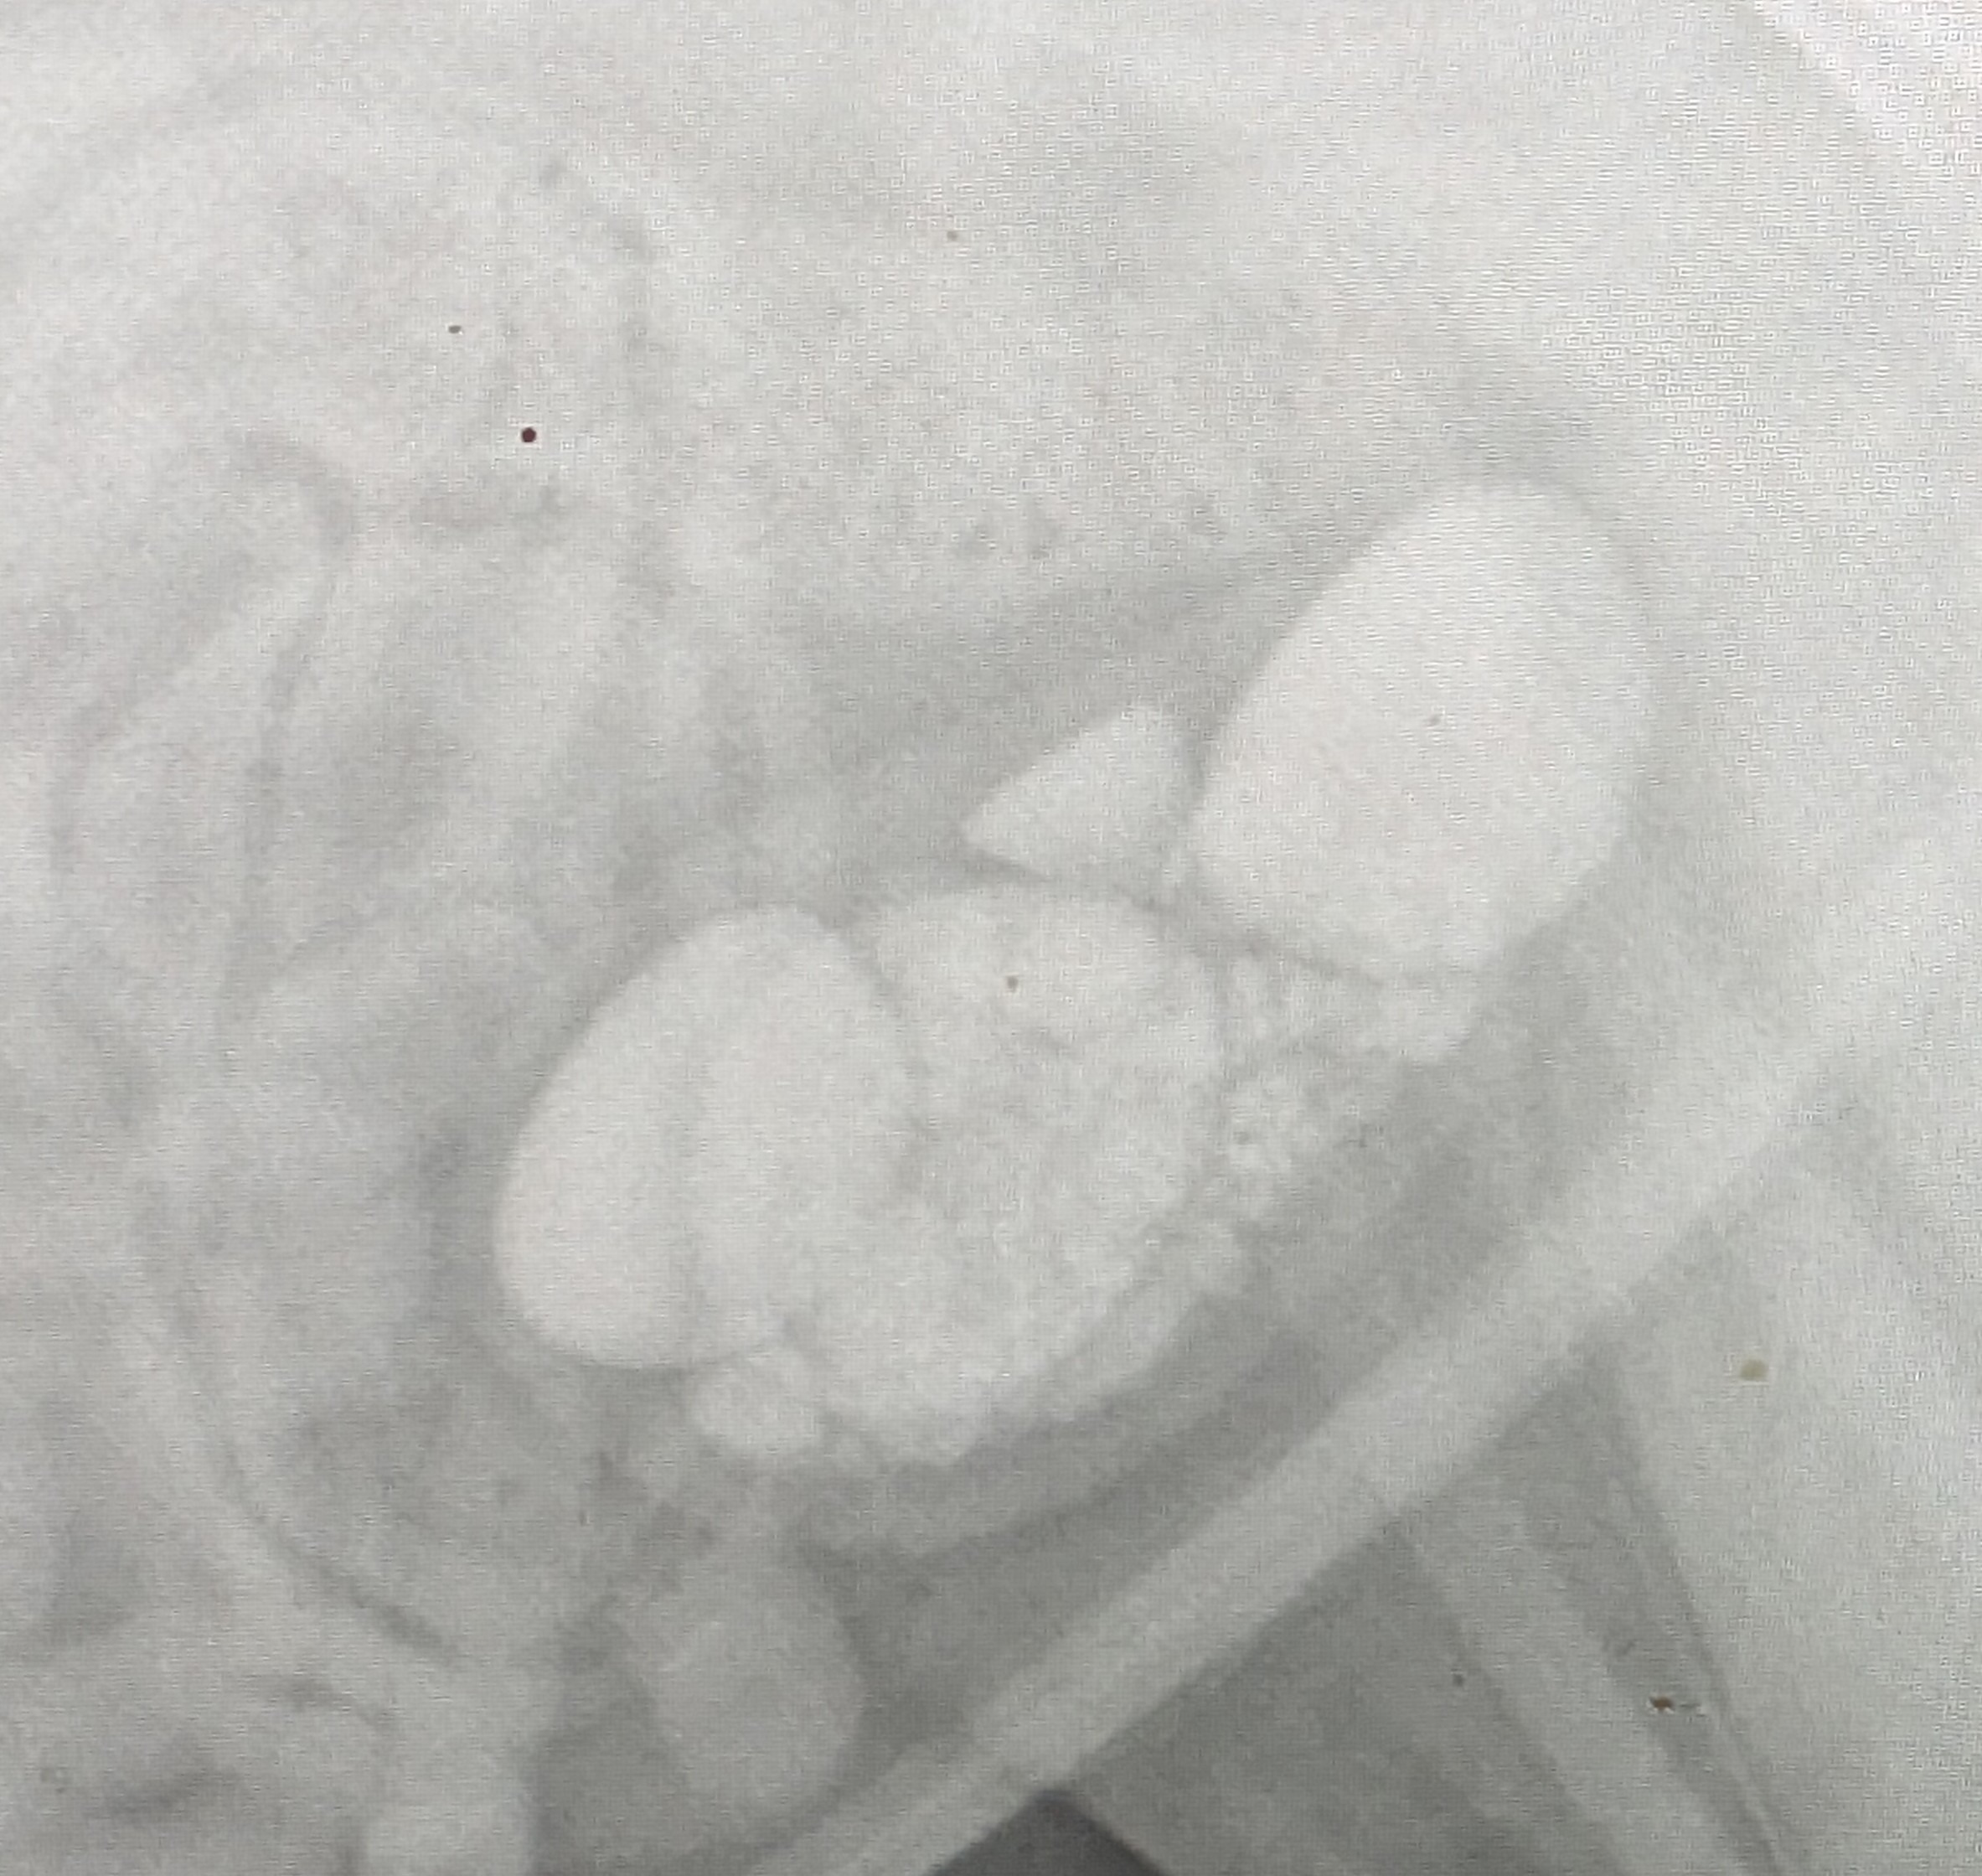

I'm doing everything I can to save my, dog im asking for support. My dog, Lola, needs a life saving procedure called a cystotomy. This surgery will help Lola by removing her large and extremely painful bladder stones. Her condition has been constantly deteriorating with her losing over 30 pounds in that year, which is an obvious signal for her declining health. The veterinarian in charge of Lola’s care, Dr. Sukhbir Singh, has said that Lola’s condition is extremely dangerous and life threatening. Without this surgery, Lola’s quality of life, and her life itself, is at risk. However, as with any procedure, this surgery is too expensive for me to pay by myself I'm working all available hours given to me but unfortunately with unforeseen and expensive car repairs and the costly vet appointments to get this diagnosis, my financial burden has become overwhelming . Please help me in the fight for Lola's life